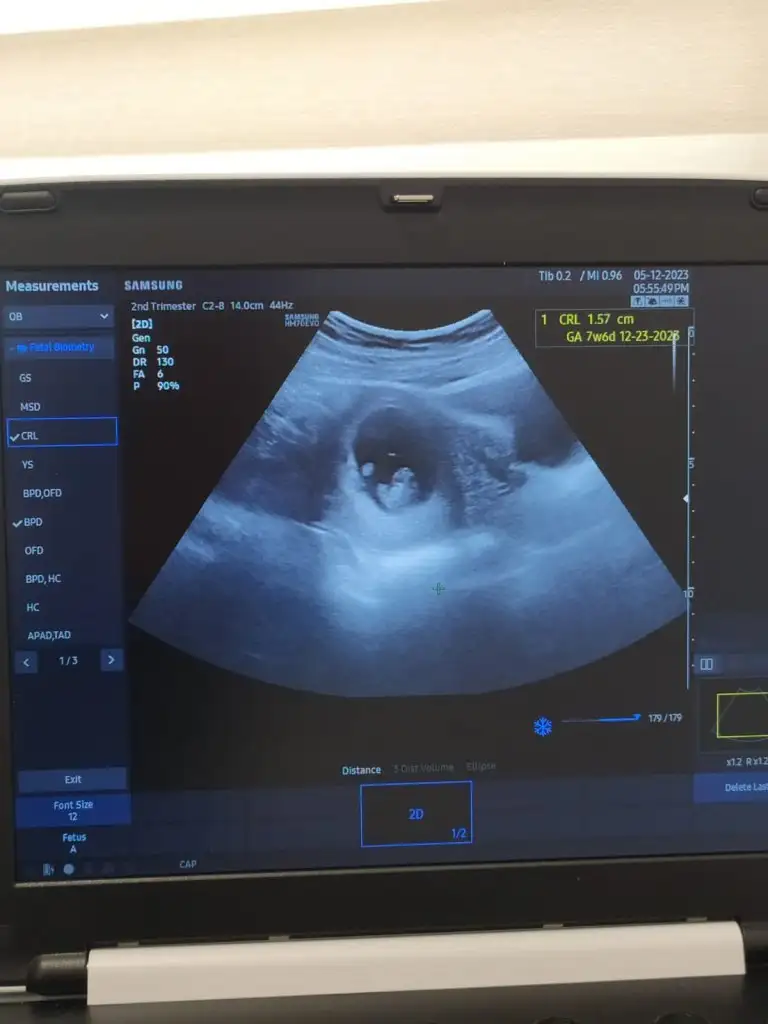

canim yas kac risk cikar diye test istememis ya peki testte olumsuz cikarsa bu gercekten sagliksiz olacagi icin mi yoksa yaniltabilecegi icin mi boyle dedi doktorun ilk bebek mi ins . bir de folik asit degerin kac cikti dolik asit ilac kullaniyor musun yoksa sadece gidalardan mi

38

Testin doğruluk payı 85 zaten.

Yaş faktörü sebebiyle ufak da risk çıksa ben stres olurum. Yapımı biliyor doktor. Kaygılı panik bir insanım.

DNA yaptır daha iyi illa yaptıracaksan dedi.

Yapılan yerin kağıdını verdi.

İlk değil

25 yaşında ve 27 yaşında da hamile oldum.

O zaman ikili üçlü ne var ne yok bütün testleri yaptırdım çok şükür o zaman hepsi temiz çıkmıştı.

35 üstü hamilelikler için riskli gözüyle bakılıyor.